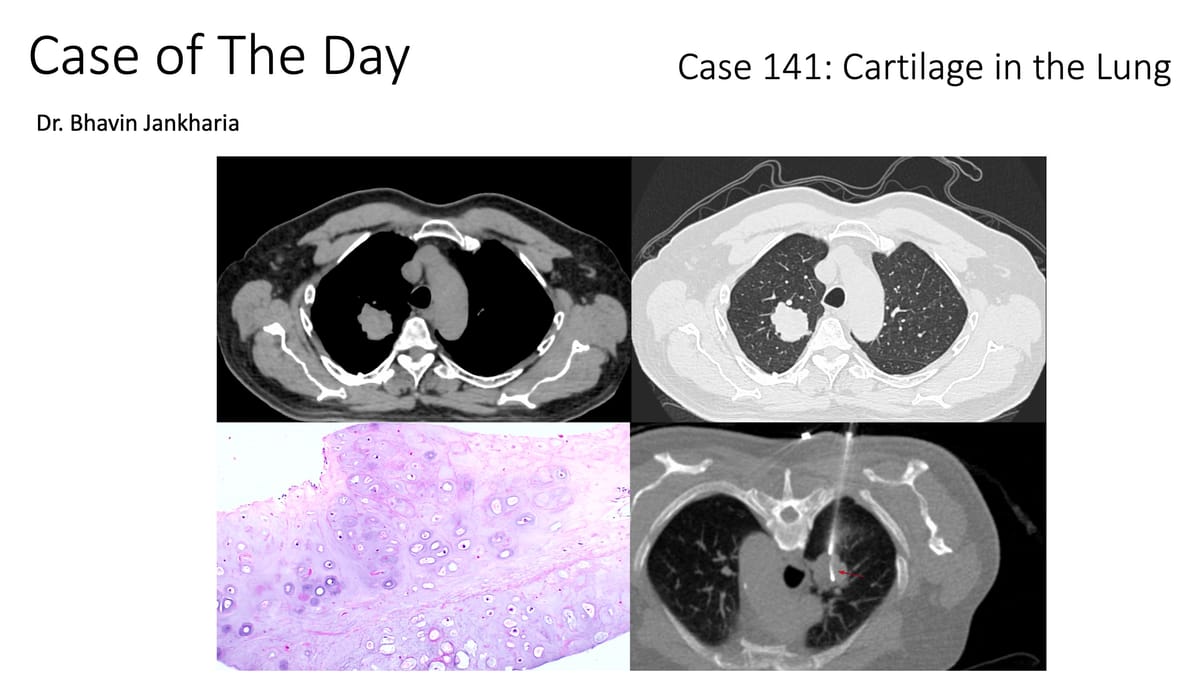

Similar case.

Similar Cases